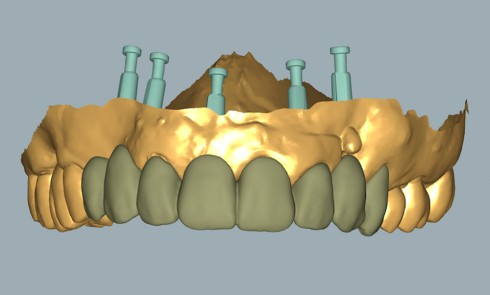

Les avancées dans la réhabilitation implantaire à l’aide du numérique sont devenues un point d’intérêt scientifique lors de ces dernières...Traitement du sourire « pauvre »